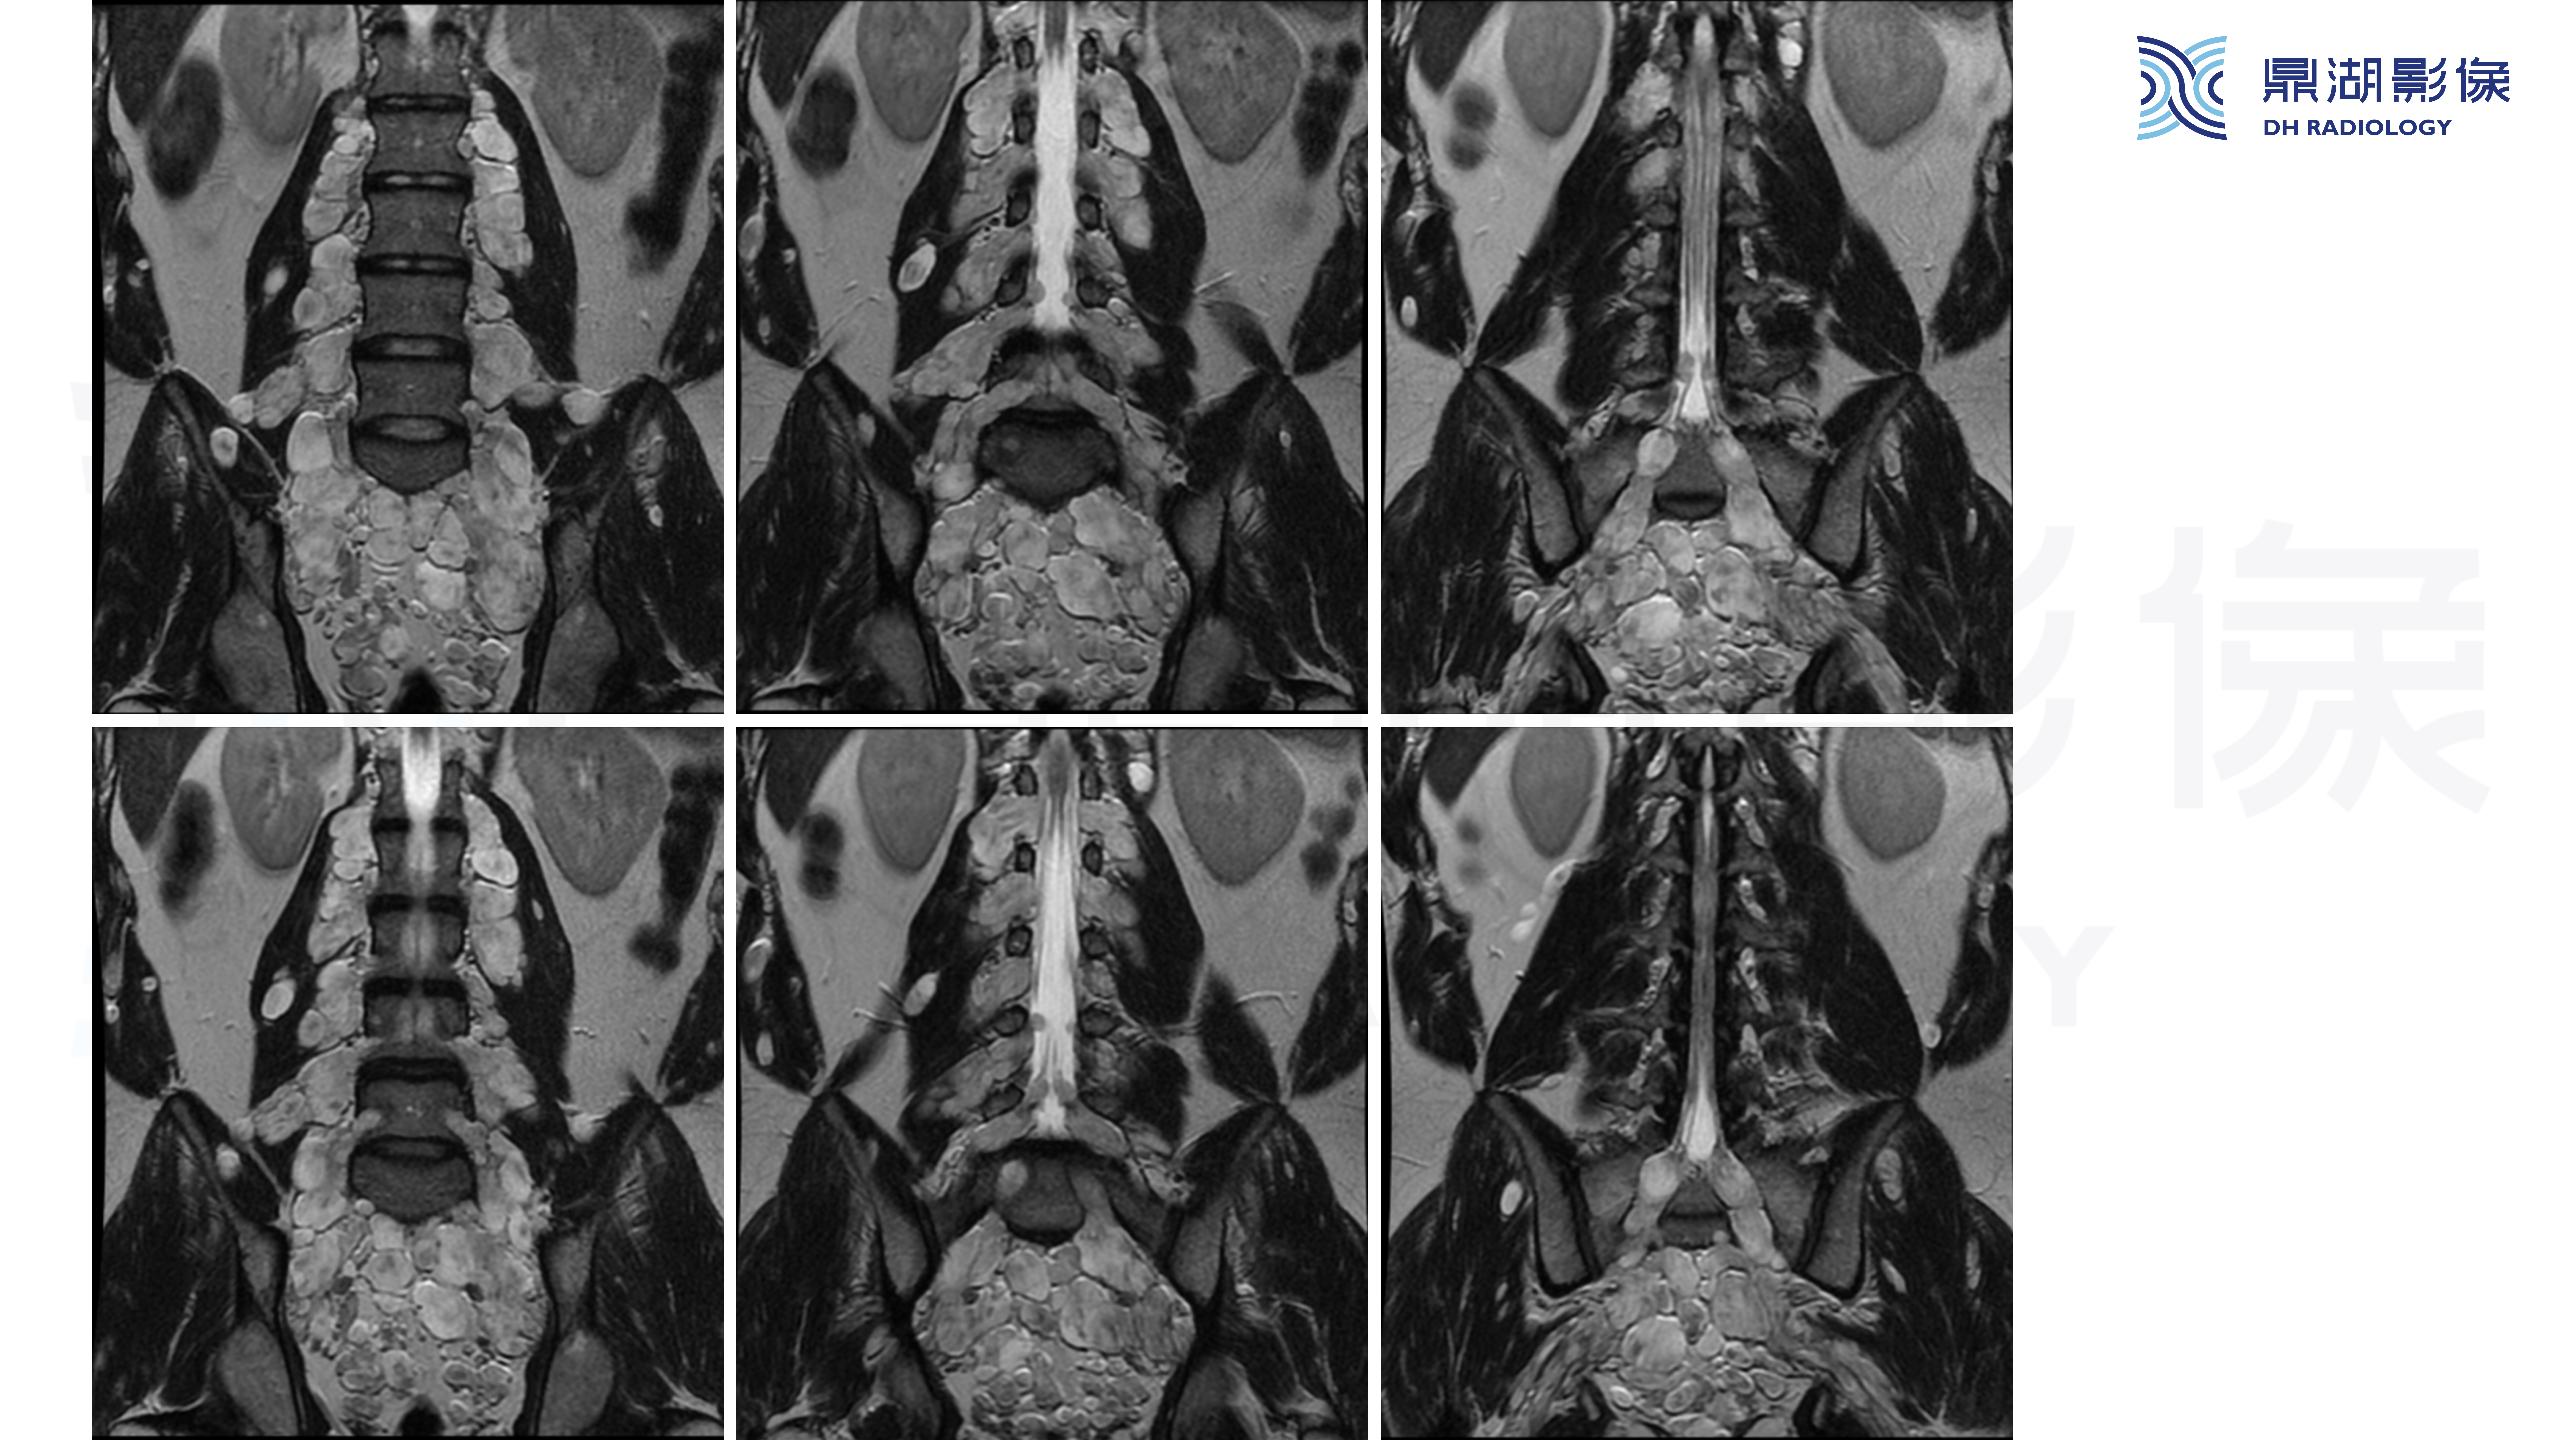

神经纤维瘤病(NF1)